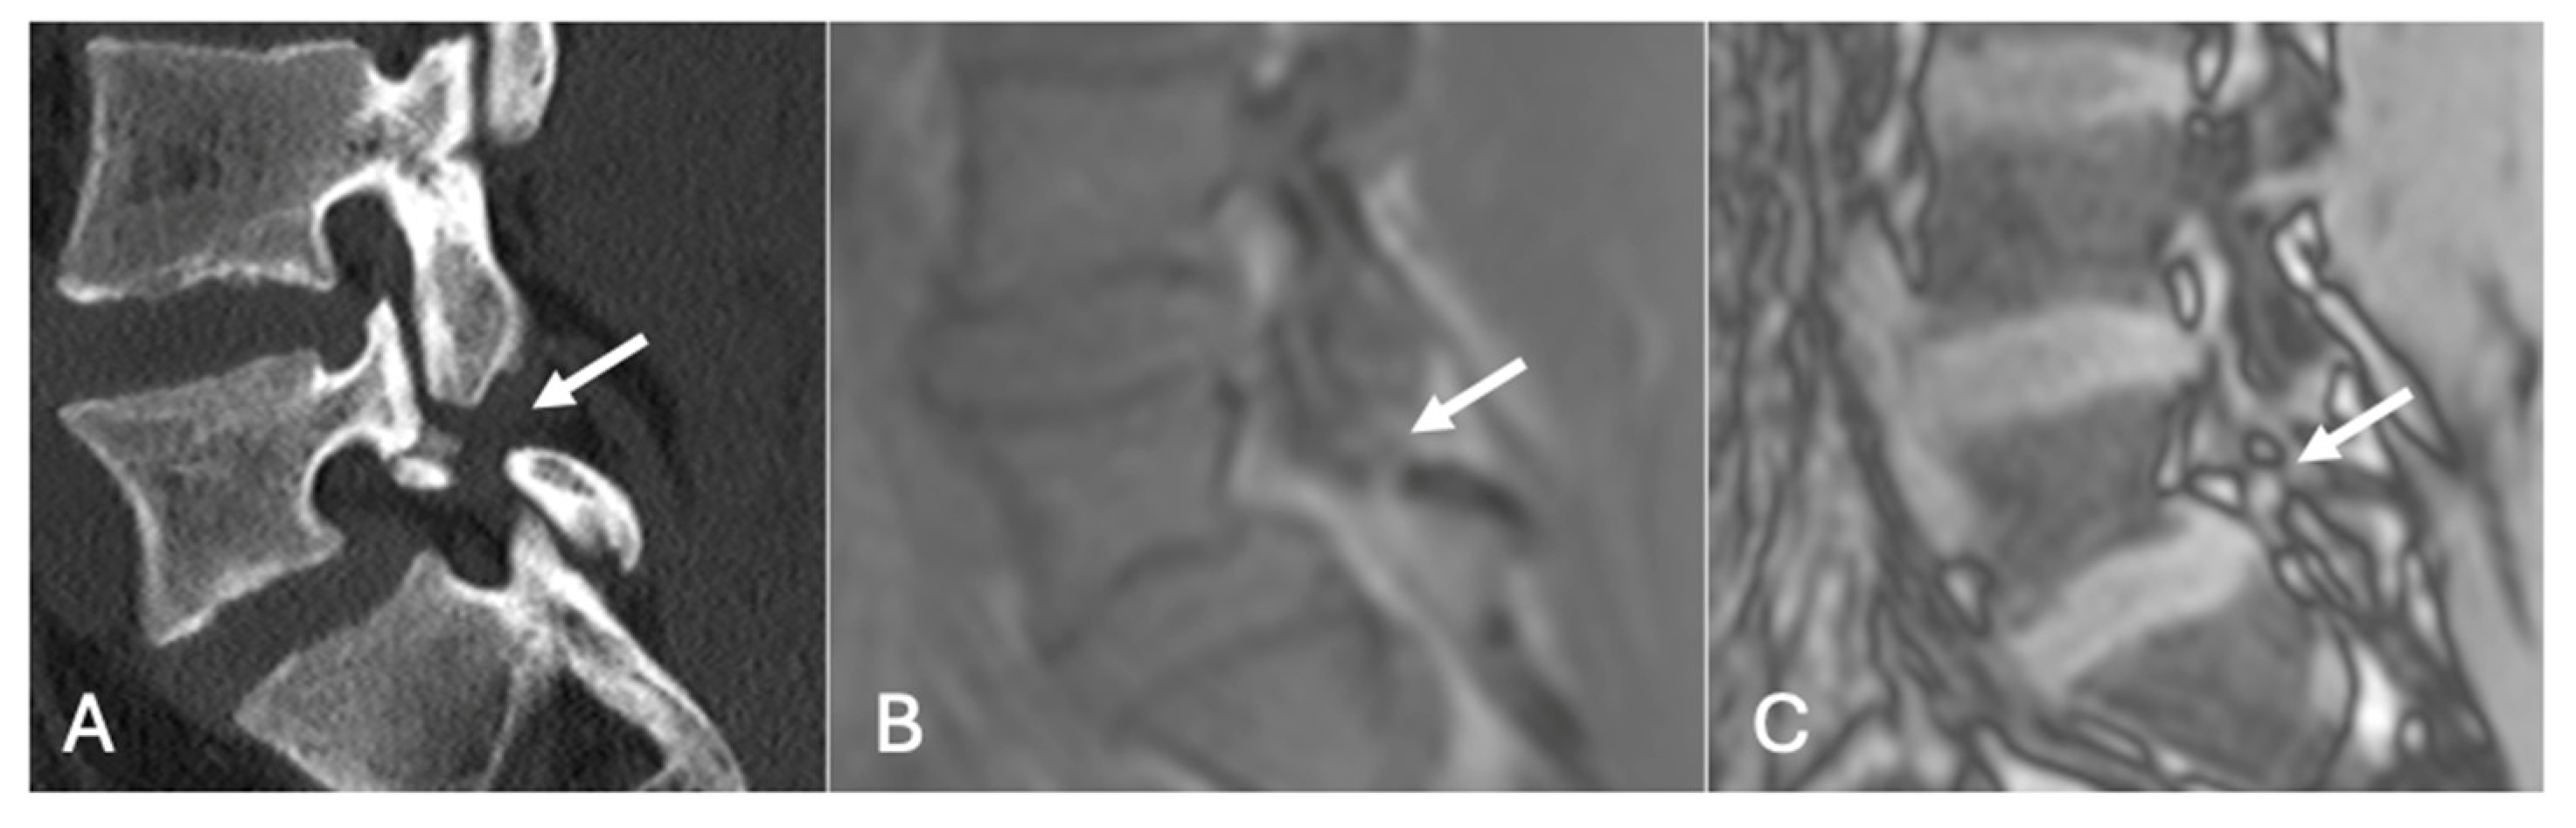

Figure 19.

Pars defect assessment CT image (A) and chemical shift in-phase (B) and out-of-phase (C), showing pars defect of L5 (arrow).

Figure 20.

Pars defect assessment sagittal CT image (A) and chemical shift in-phase (B) and out-of-phase (C), showing intact pars of L4 (arrow).